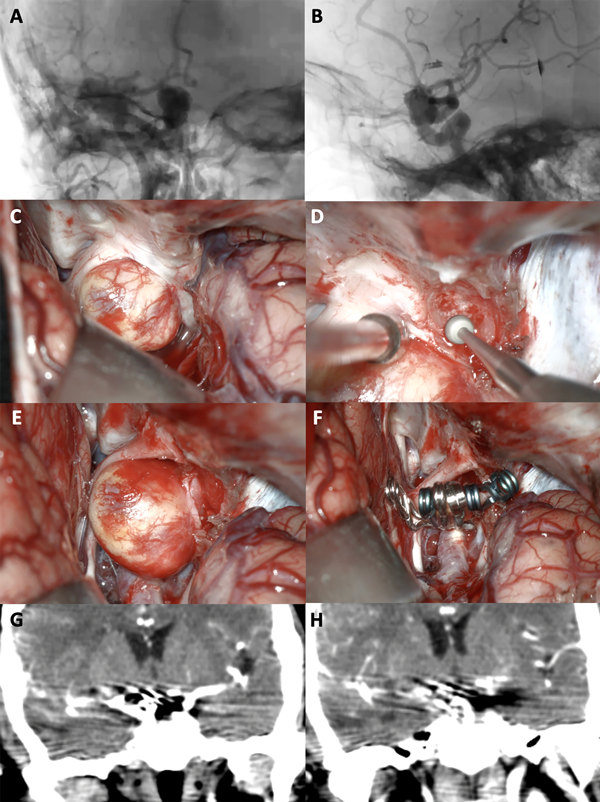

Figura 6. A-B: Se aprecia una arteriografía cerebral en vista AP y lateral que evidencia un aneurisma carótido oftálmico derecho gigante. C-F: Fotografías intraoperatorias. Observamos la cisterna óptico-carotidea; es notorio el gran efecto de masa del saco aneurismático sobre el nervio óptico. Posteriormente se realizó una clinoidectomía anterior total y sección del anillo dural distal logrando una adecuada exposición del cuello del aneurisma. Se muestra la exclusión del aneurisma con una técnica de reconstrucción vascular con múltiples clips. G-H: Imágenes de angio tomografía post operatoria que evidencia la exclusión completa del aneurisma, sin complicaciones asociadas.

Figura 7. A-B: Se aprecia una arteriografía cerebral que evidencia un aneurisma carótido oftálmico izquierdo gigante. Es notoria la presencia de una ampolla (“bleb”) de gran tamaño. C-F: Fotografías intraoperatorias. Observamos la cisterna óptico-carotidea donde es visible el saco aneurismático. Dado el tamaño de la lesión se realiza una clinoidectomía anterior total y sección del anillo dural distal logrando una adecuada exposición del cuello del aneurisma. Se muestra la exclusión del aneurisma con múltiples clips. G-H: Imágenes de arteriografía cerebral post operatoria que evidencia la exclusión completa del aneurisma con preservación de la arteria oftálmica.